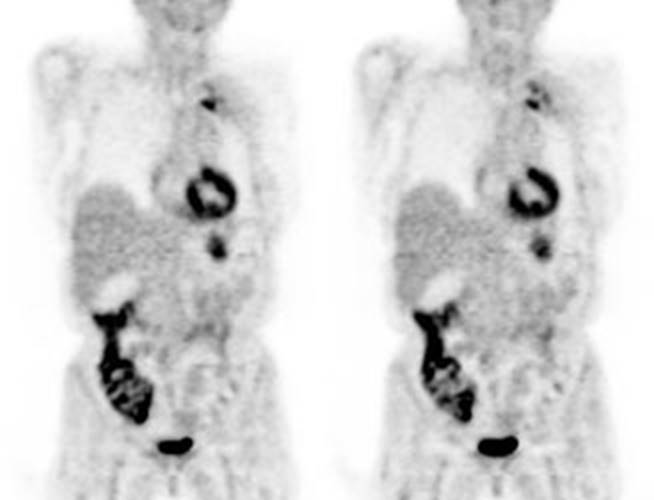

Figure 5 - Genitourinary activity: The image below demonstrates normal

renal and hepatic activity.

Figure 6 - Genitourinary activity: The image below

demonstrates activity within the collecting system of a transplanted kidney

(black arrows). This should not be mistaken for an abnormality.

Figure 7 - Bladder cancer: Despite urinary excretion

of the radiotracer, this patients bladder cancer

(white arrows) is readily identified on the PET scan (black arrows). In

general, however, urinary excretion of FDG limits evaluation of urinary tract

malignancy